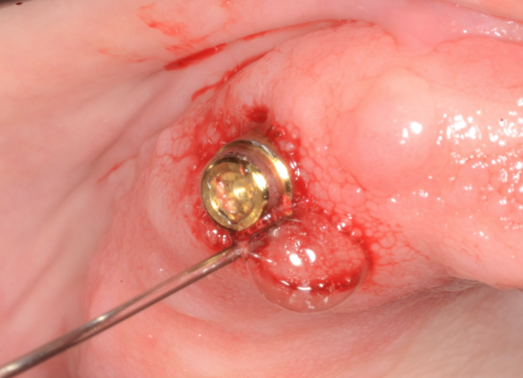

Radiographs

Given patient concerns about radiation exposure, it is important to know how, when, and why radiographs should be taken. Although there are concerns about radiation, radiographs make it possible to determine bone levels at baseline—ie, at implant and restoration insertion—and to monitor them over time. Vertical radiographs should be as parallel as possible to the implant body, so that the implant threads are clearly visible. Typically, periapicals should be taken once a year around dental implants. Figure 3 and Figure 4 shows bone loss up to the fifth and sixth thread.

Radiographs showing bone loss around an implant.

Figure 3

Figure 4